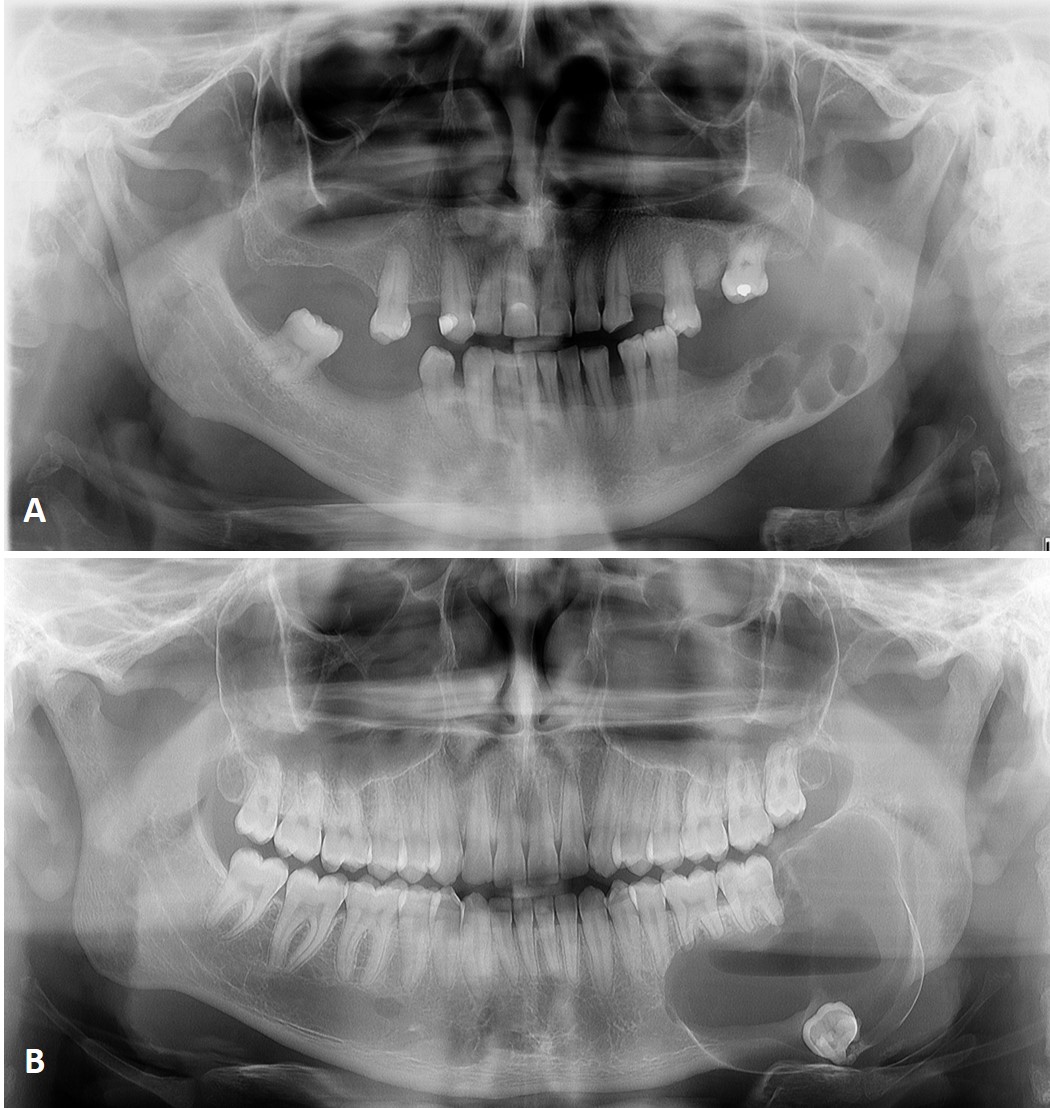

Diagnostic value of magnetic resonance imaging in the analysis of ameloblastoma: report of two cases

Ameloblastoma is an odontogenic tumor that shares clinical and imaging characteristics with other lesions of the jaws, such as odontogenic keratocyst, which makes the diagnosis difficult. However, in addition to radiographic and tomographic examinations, Magnetic Resonance Imaging (MRI) has been increasingly used, contributing with relevant additional information about the differentiation between solid and liquid components of the lesion. This case report was conducted to present two variations of ameloblastoma and discuss the radiographic, tomographic and MRI contribution in the differential diagnosis between ameloblastoma and odontogenic keratocyst.The signal intensity in T1-weighted MRI revealed internal fluid content in both cases, which was important in the differential diagnosis with other intraosseous lesions such as odontogenic keratocysts. This is probably due to the presence of keratin that increases the viscosity of the content and also for an intermediate signal intensity signal in T2-weighted MRI. Therefore, MRI revealed important internal characteristics of the reported lesions, which was very useful in the establishment of the differential diagnosis with other lesions.